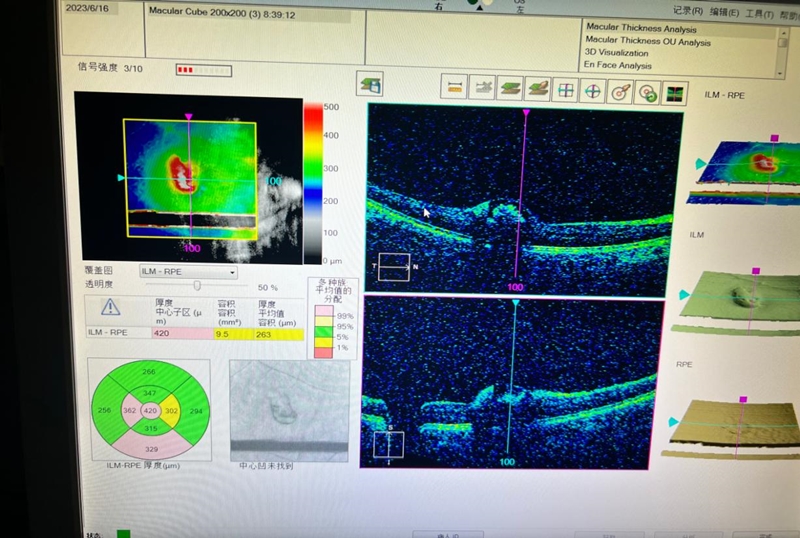

近日,薛女士出现视物模糊,重影,流泪畏光,视力下降等不适。经苏州高新区人民医院眼科医生仔细询问了解到,薛女士往日视力都很好,在参加了一场明星的演唱会后,由于坐在前排,现场舞台激光灯经常对着自己的眼睛照射。当时觉得那个激光光线不强,就没有在意。医生为薛女士做了全面检查,验光检查发现,小薛左眼矫正视力能达到正常 1.0,右眼矫正视力仅只有0.12。而眼底检查发现,右眼的黄斑区明显出血。为了明确黄斑部病变性质,医生给小薛进一步做了视网膜的光学相干断层成像检查(OCT 检查),结果显示,其右眼黄斑区中央可见病灶处外层视网膜断裂,感光细胞受损。

该院眼科主任祝莲表示,小薛是典型的视网膜激光损伤。很遗憾的是,激光的损伤已经造成了视网膜视细胞不可逆的损伤。以目前的医学水平,右眼的视力下降是不可恢复的。